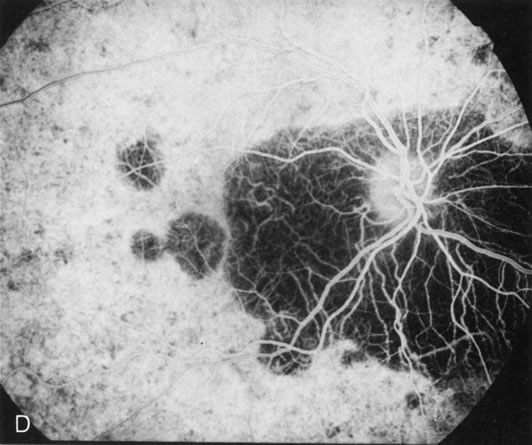

HEREDITARY HEMORRHAGIC MACULAR DYSTROPHY (PSEUDOINFLAMMATORY MACULAR DYSTROPHY OF SORSBY)

FA plays an important role in the understanding of this rare disorder. In the earliest manifestations of the disease, FA shows a single, isolated choroidal neovascular membrane unassociated with other causes of a membrane, such as drusen or angioid streaks (Fig. 13).25 Presumably this membrane is the cause of the subsequent hemorrhagic maculopathy with secondary disciform scarring, occurring initially in the macula but often extending throughout the retina.

Fig. 13. Hereditary hemorrhagic macular dystrophy (pseudoinflammatory macular dystrophy of Sorsby). Fluorescein angiography in this family member demonstrates that the earliest finding is an isolated choroidal neovascular membrane B). Despite laser photocoagulation, a hemorrhagic maculopathy developed in this eye (C, D) and eventually a disciform scar (E) formed, as it had in the fellow eye, and in the eyes of other affected family members.

Abnormal choroidal perfusion, manifested on FA as a delay in choriocapillaris filling, has been seen in the restudy of some of Sorsby's initial pedigrees.26 This unusual pattern has been related to the histopathologic finding of a “confluent, lipid-containing, amorphous deposit found between the basement membrane of the RPE and the inner collagenous layer of Bruch's membrane.”27